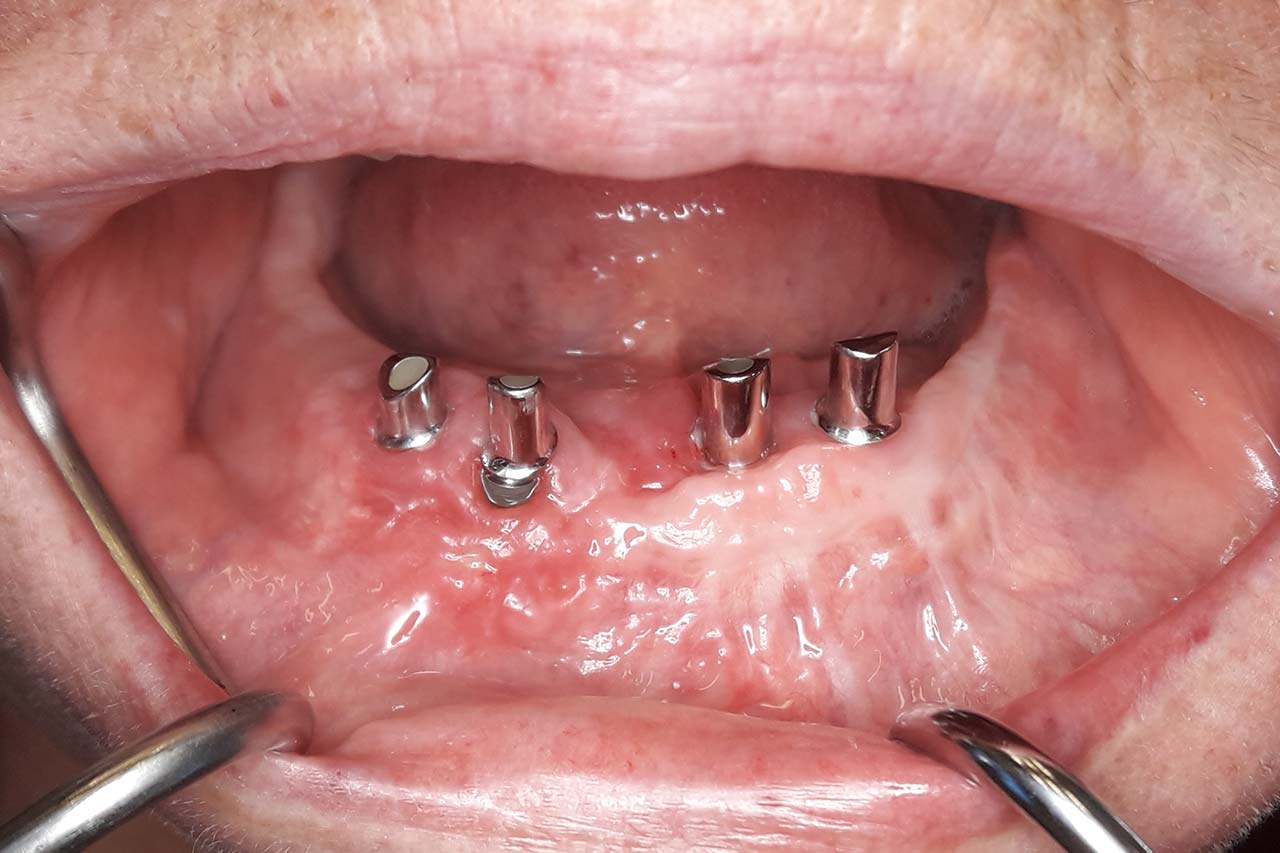

„Implantat-Chirurgie kompromittierter Patienten und was können wir für Gesunde daraus lernen?

OÄ Dr. Marie-Sophie Katz, Aachen

„Implantatprothetik – Unterschiede zwischen kompromittierten und gesunden Patienten“

Prof. Dr. Sven Reich